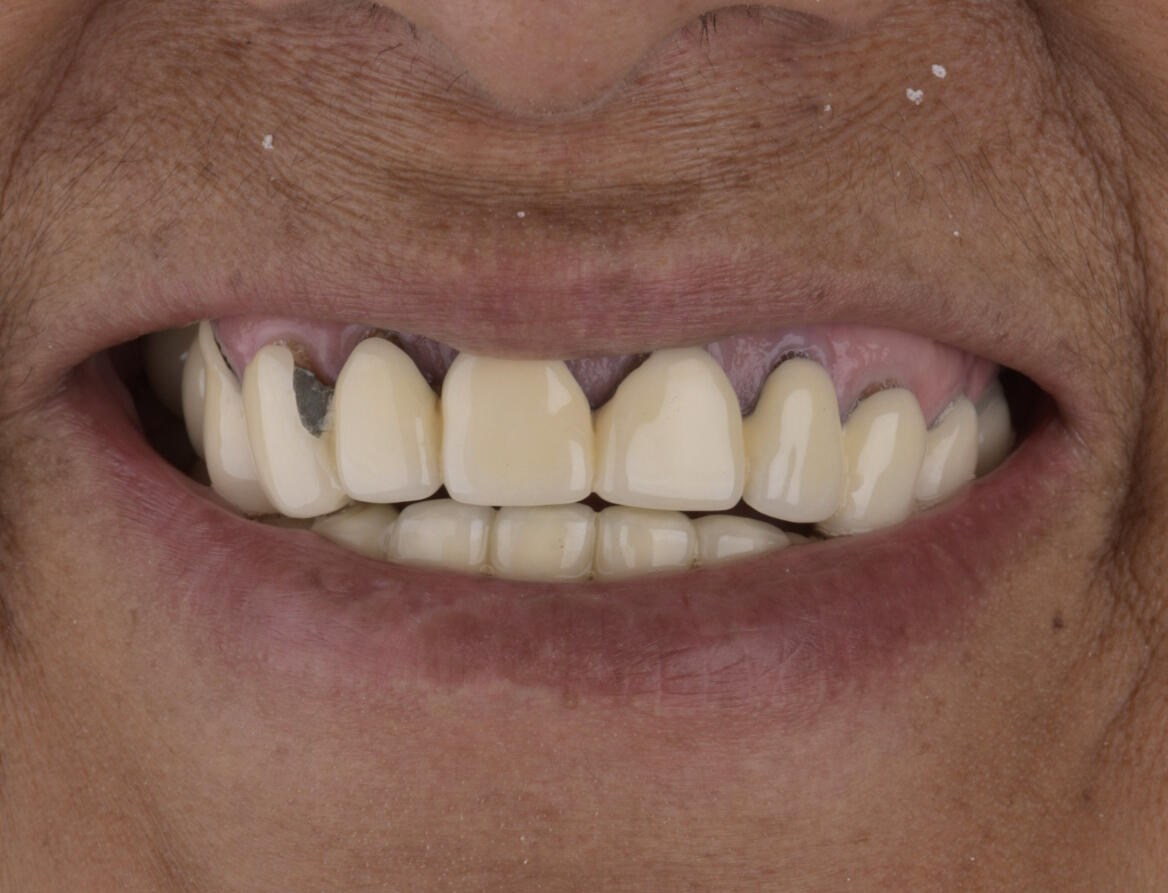

Complex Prosthetic Rehabilitation in an International Patient with Prosthetic Failure and Periodontal ComplicationsA patient from the state of Georgia (United States) sought specialized dental treatment due to complex failure of existing fixed dental prostheses. Clinical examination revealed prosthetic fractures, gingival inflammation, food impaction, compromised periodontal support tissues, and disruption of the smile line and occlusal harmony.A comprehensive prosthetic and periodontal treatment protocol was implemented, focusing on biological compatibility, functional occlusion, periodontal stabilization, and esthetic reintegration. Advanced restorative techniques and biomaterials were utilized to ensure long-term functional and biological stability.Post-treatment outcomes demonstrated improved periodontal health, occlusal function, and esthetic balance of the smile.This international case reflects transnational recognition of clinical expertise and highlights the importance of high-level interdisciplinary restorative and periodontal rehabilitation in complex prosthetic failures.